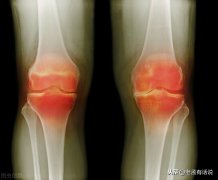

最近由于天气寒冷许多膝关节疼痛的患者来门诊就诊。那么冬季为什么是膝关节关节炎症状加重的一个季节呢?今天给大家科普一下。 第一,在自然状态下我们膝关节本身的血流就比较